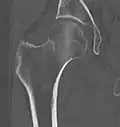

X-ray showing a suspected compressive subcapital fracture as a radiodense line -

CT scan shows the same, atypical for a fracture since the cortex is coherent -

T1-weighted turbo spin echo MRI confirms a fracture, as the surrounding bone marrow has low signal from edema.